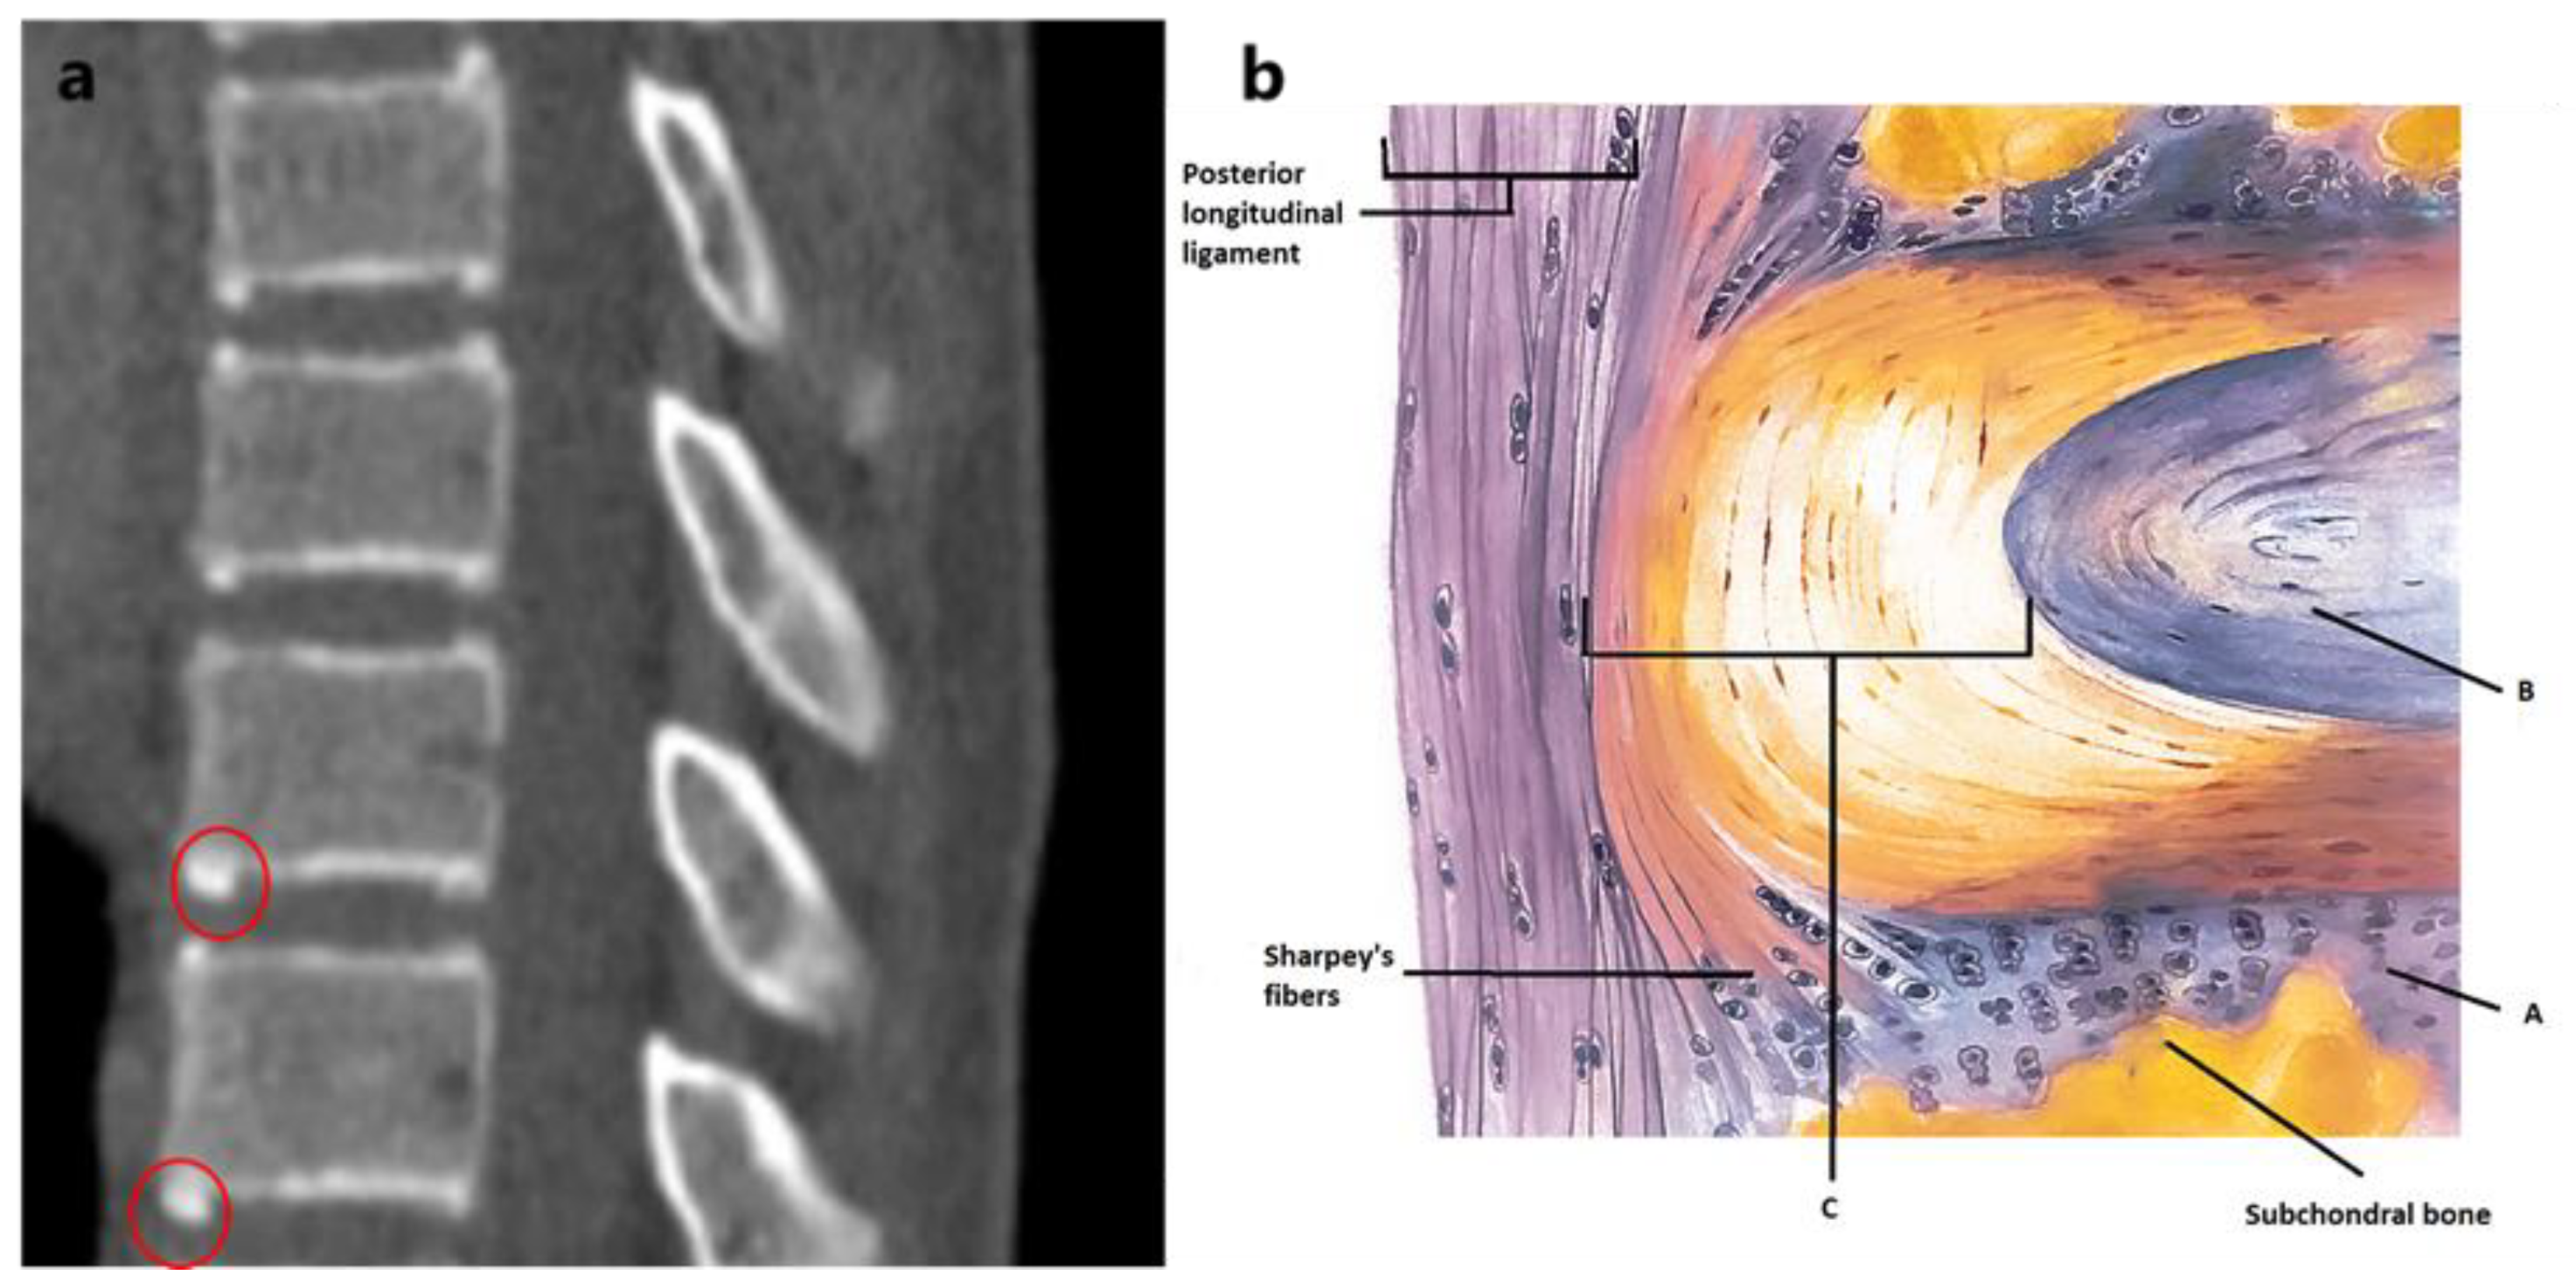

Importance of the epiphyseal ring in OLIF standalone surgery a biomechanical study on Epiphyseal Ring Function    the epiphyseal ring varies largely in size and shape along the thoracolumbar spine. To characterize and analyze the shape. To characterize and analyze the shape and size of the epiphyseal ring, to better understand its function. The function of the groove of ranvier is to contribute chon.   a descriptive study of the epiphyseal ring's structural design along the. Epiphyseal Ring Function.

(PDF) The Epiphyseal Ring A Long Anatomical Structure with Signifi cant Physiological Epiphyseal Ring Function  The function of the groove of ranvier is to contribute chon.   a descriptive study of the epiphyseal ring's structural design along the thoracolumbar spine.  ranvier and a perichondrial ring called the ring of lacroix5 (figure 2).  a descriptive study of the epiphyseal ring’s structural design along the thoracolumbar spine.   ossification and fusion of each ring apophysis. Epiphyseal Ring Function.